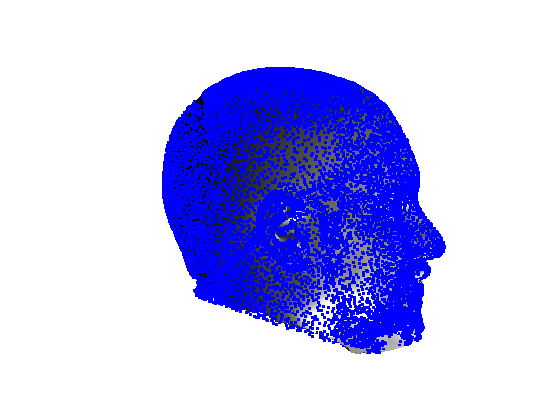

Following this, OSNR ICP iterates over a set of decreasing mesh stiffnesses (typically 10), until the registration between the template and the scan is below some error or a maximum number of iterations is reached. Figure 28 shows a selection of template warp results. The template appears to be accurately warped onto the scan, at least in the normal direction of the surfaces, it is not possible to see error tangential to the surface. Furthermore, we have noted errors on some scans on the ears. To improve these we need a method of automatically landmarking the ears, which is an area for further work.

|

|

|

|

|

|

|

|

The first two modes of head variation are shown in figures 29 and 30. These include the cranial height / facial angle mode and the (almost) pure size mode, as seen in the sagittal profile model.